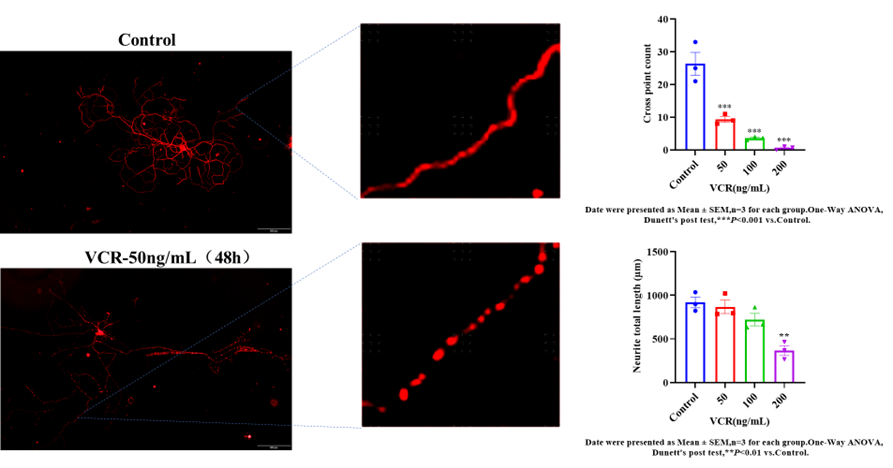

原代背根神经元(DRG)细胞模型 |

长春新碱诱导 |

细胞活力、神经毒性 |

l 模拟化疗药物引起的直接神经毒性

l 支持药物筛选、机制研究、阳性药验证

l 可定制化造模方案(浓度梯度、时间梯度)

化疗痛(长春新碱) |

腹腔注射长春新碱 |

微管抑制剂→周围神经毒性 |

机械痛阈值、热痛阈值 |